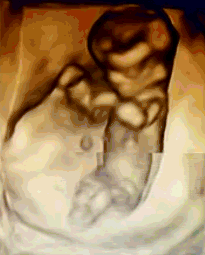

NT是胎儿颈部半透明膜的缩写,是10~13孕周围绕在胎儿颈项后部流动性的半透明蛋白膜。它的厚度与胎儿DS缺陷正相关,并可以通过超声成像测量。

NT排畸检查是指胎儿颈后部皮下组织内液集聚的厚度的检查。通过B超测定颈项透明层厚度,便于及早发现唐氏儿和先天性心脏病的胎儿,并及时予以干预。